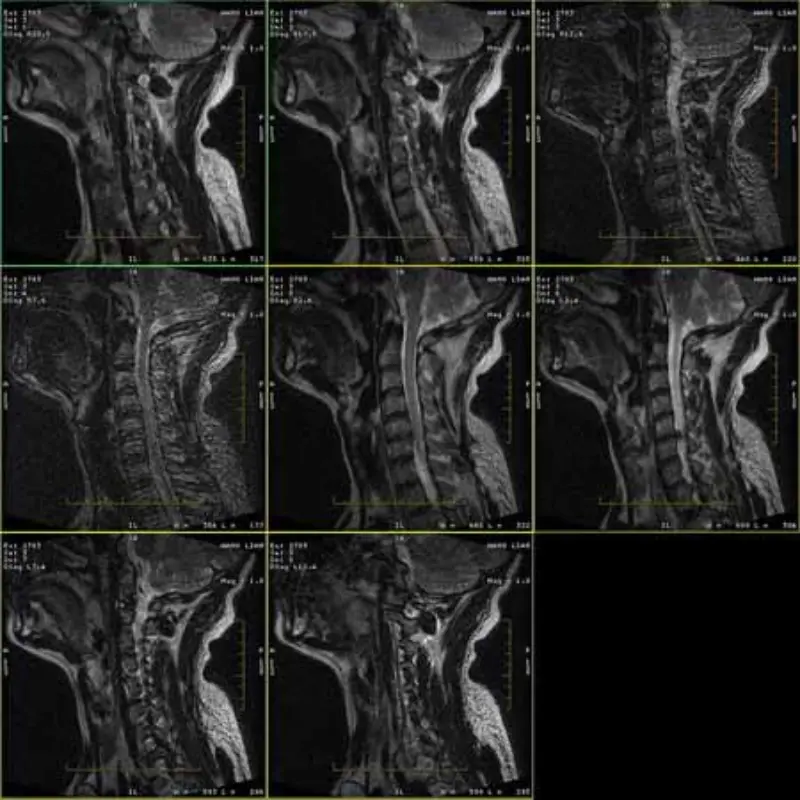

Imaginile protocoalelor FRFSE și GRE au fantomă și uneori imagini SNR scăzute apar într-o serie. Dar imaginile de protocol SE sunt normale.